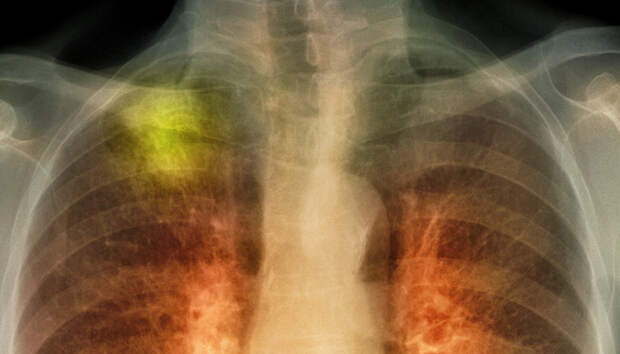

За минувшие сутки с воспалением легких в республике госпитализировано пять человек Пять человек за сутки госпитализированы с внебольничной пневмонией в Карелии, сообщает оперштаб по борьбе с распространением коронавирусной инфекции. Летальных исходов не зарегистрировано. Начиная с 1 апреля, с внебольничной пневмонией госпитализированы 1397 пациентов, 78 человек умерли (с учетом пациентов, госпитализированных ранее указанного периода).